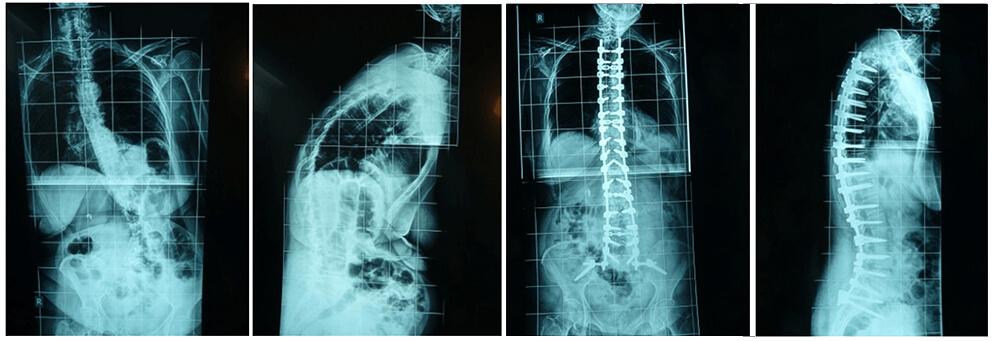

Εικ. 3: α. Προεγχειρητική και β. Μετεγχειρητική φωτογραφία της στάσης του σώματος (πριν και μετά τη διορθωτική χειρουργική επέμβαση). Καθοριστικό σημείο για την επιτυχή χειρουργική αντιμετώπιση της σκολιωτικής παραμόρφωσης του ενήλικα είναι η αποκατάσταση της οβελιαίας ισορροπίας του σώματος.